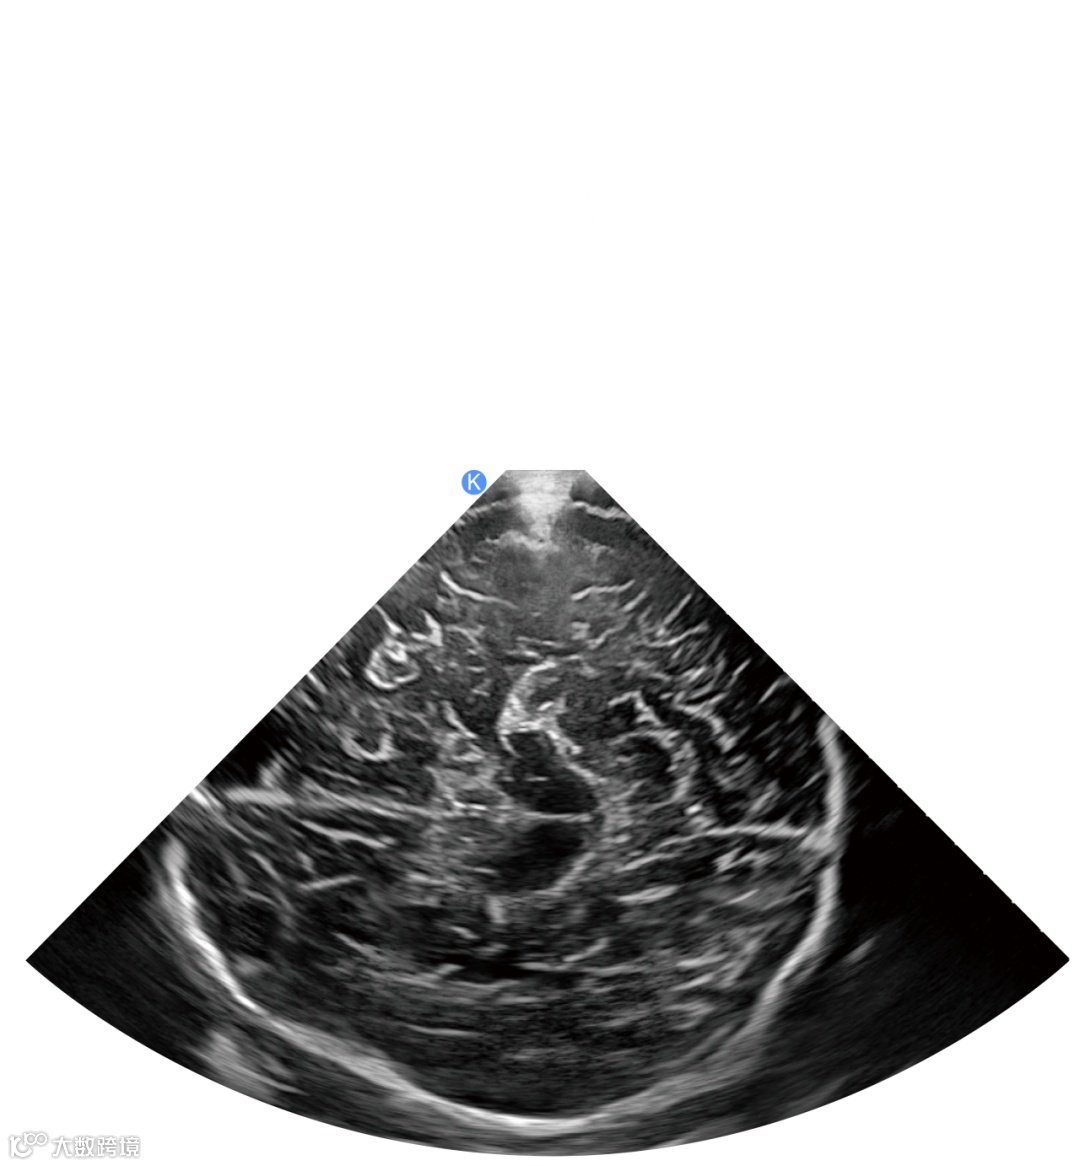

鲲为独创的kOS成像平台,运用独特的EP全模态平面波、SRBF超分辨波束合成以及UP超穿探头,依托于强大的GPU处理能力,在业内首次打破了空间分辨力、时间分辨力和穿透力三大参数的制约关系,实现了超声影像技术的突破性革命。

国内外客户和专家们对鲲为的反应出奇的一致:都被鲲为图像展现的超高穿透力和深部分辨率深深震撼到了,颅脑超声诊疗时代,已被鲲为开启!

新科技的出现让超人们欣喜,在会议现场竟然兴起“颅脑打图风”,各友商纷纷拿起探头,尝试自家产品经颞窗扫查颅脑超声图像表现。作为超声新秀,鲲为的初次亮相便引起行业的众多关注,凭借超分辨颅脑图像的精彩呈现,吸引各专家、同行纷纷到鲲为展位上操作体验。